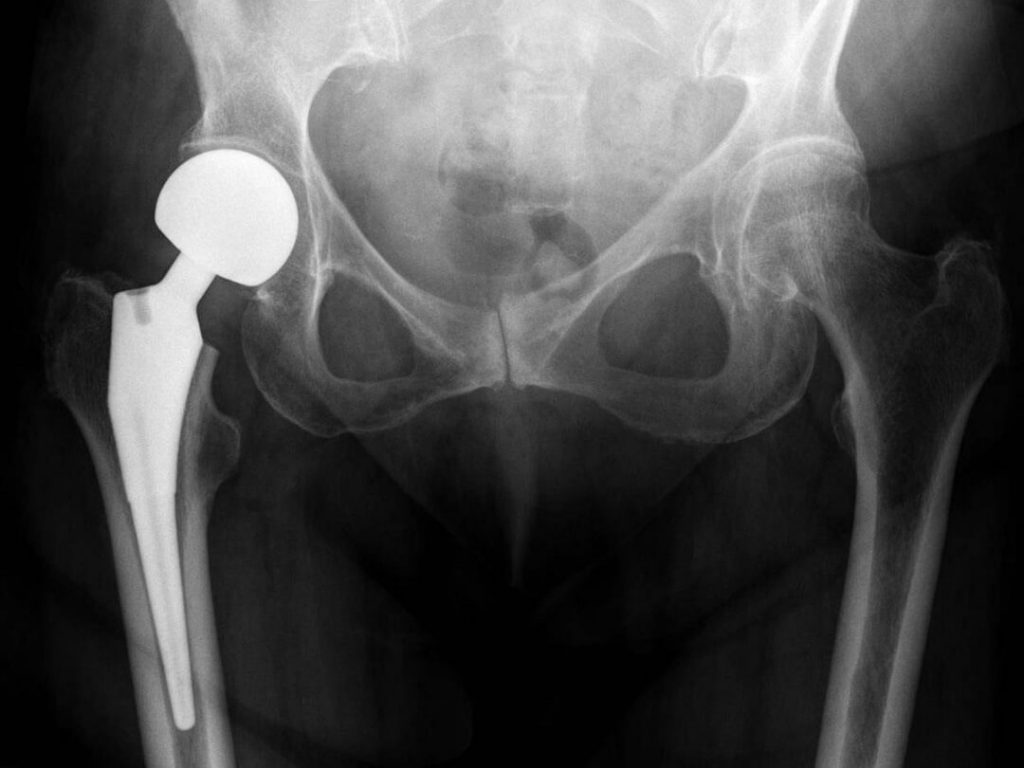

Kalça protezi ameliyatı, temelde kalça ağrısını gidermek için yapılan cerrahi bir işlemdir. Kalça eklemi bir top (uyluk kemiğinin tepesi) ve yuvadan (kalça kemiği) oluşur. Kalça protezi ameliyatında eklemin bu parçalarından biri veya her ikisi yapay implantlarla değiştirilir. Kalça protezi ameliyatının amacı, kişinin ağrısız bir şekilde günlük aktivitelere devam edebilmesini sağlamaktır.

Kalça protezi ameliyatında, hasarlanmış kemik ve kıkırdak dokular çıkartılarak yerlerine protez bileşenler konulur.

Uyluk kemiği (femur) baş kısmı çıkarılır, yerine metal bir protez konulur. Protezin kök kısmı uyluk kemiğinin boşluk olan merkezine gömülür. Metal veya seramikten yarım küre şeklindeki baş kısmı protezin üst kısmında yerleşiktir.

Femur başının oturduğu leğen kemiği çukurunun (asetabulum) zedelenmiş kıkırdağı çıkarılarak yerine metal soket konulur. Soket vida veya sementle yerine sabitlenebilir. Baş ve soketin birbiri üzerinde sürtünmeden hareket edebilmesi için plastik, seramik veya metal bir iç astar (spacer, liner) kullanılır.